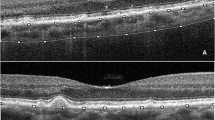

Representative case of dot-type subretinal drusenoid deposit (SDD) (A–D) and ribbon type SDD (E–H). (A) and (E) show color fundus photographs. Magnified insets of the SDD, enclosed in green boxes at the bottom left corner, provide clearer visualization of each SDD type. (B) and (F) are blue peak fundus autofluorescence (FAF) images. C and G are infrared reflectance (IR) images. (D) and (H) show pointwise retinal sensitivity maps and corresponding OCT B-scans. All images are co-registered to display the same macular region. Both dot-type (A–D) and ribbon-type (E–H) SDD involve the macula, defined as more than 10 SDDs within the macula area on an OCT scan. Blue line is indicate the margins of SDD to facilitate cross-modality comparisons of SDD extent and retinal sensitivity. In the dot-type case (A–D), most SDDs are confined within the blue circle, whereas in the ribbon-type case (E–H), SDDs are located outside the blue circle. Retinal sensitivity is markedly reduced in the presence of ribbon-type SDD (H).